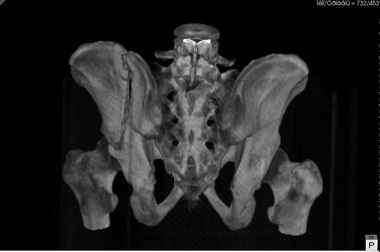

Добрый вечер уважаемые коллеги. Госпитализирован пациент с переломом таза 9-ти месячной давности (лечился где-то в районе консервативно). Помогите определиться с оптимальным вариантом хирургического доступа, фиксации.

Пациенту чуть больше сорока лет, работал в МЧС, после ДТП лечился по месту жительства консервативно. Жалобы пациента на постоянные боли в месте перелома, ощущение подвижности в месте перелома при ходьбе. Передвигается без дополнительной опоры, хромота не щадящая. Клинически отчетливо определяется патологическая подвижность крыла левой подвздошной кости. R-ммы не высылаю, сразу 3-D, если не хватит дошлю снимки.

Андрей, на 3d снимках не видно соотношение суставных поверхностей, величину диастаза в ложном суставе и состояние головки (может уже протез нужен).

Нужны стандартные снимки и срезы на уровне сустава и тела подвздошной кости.